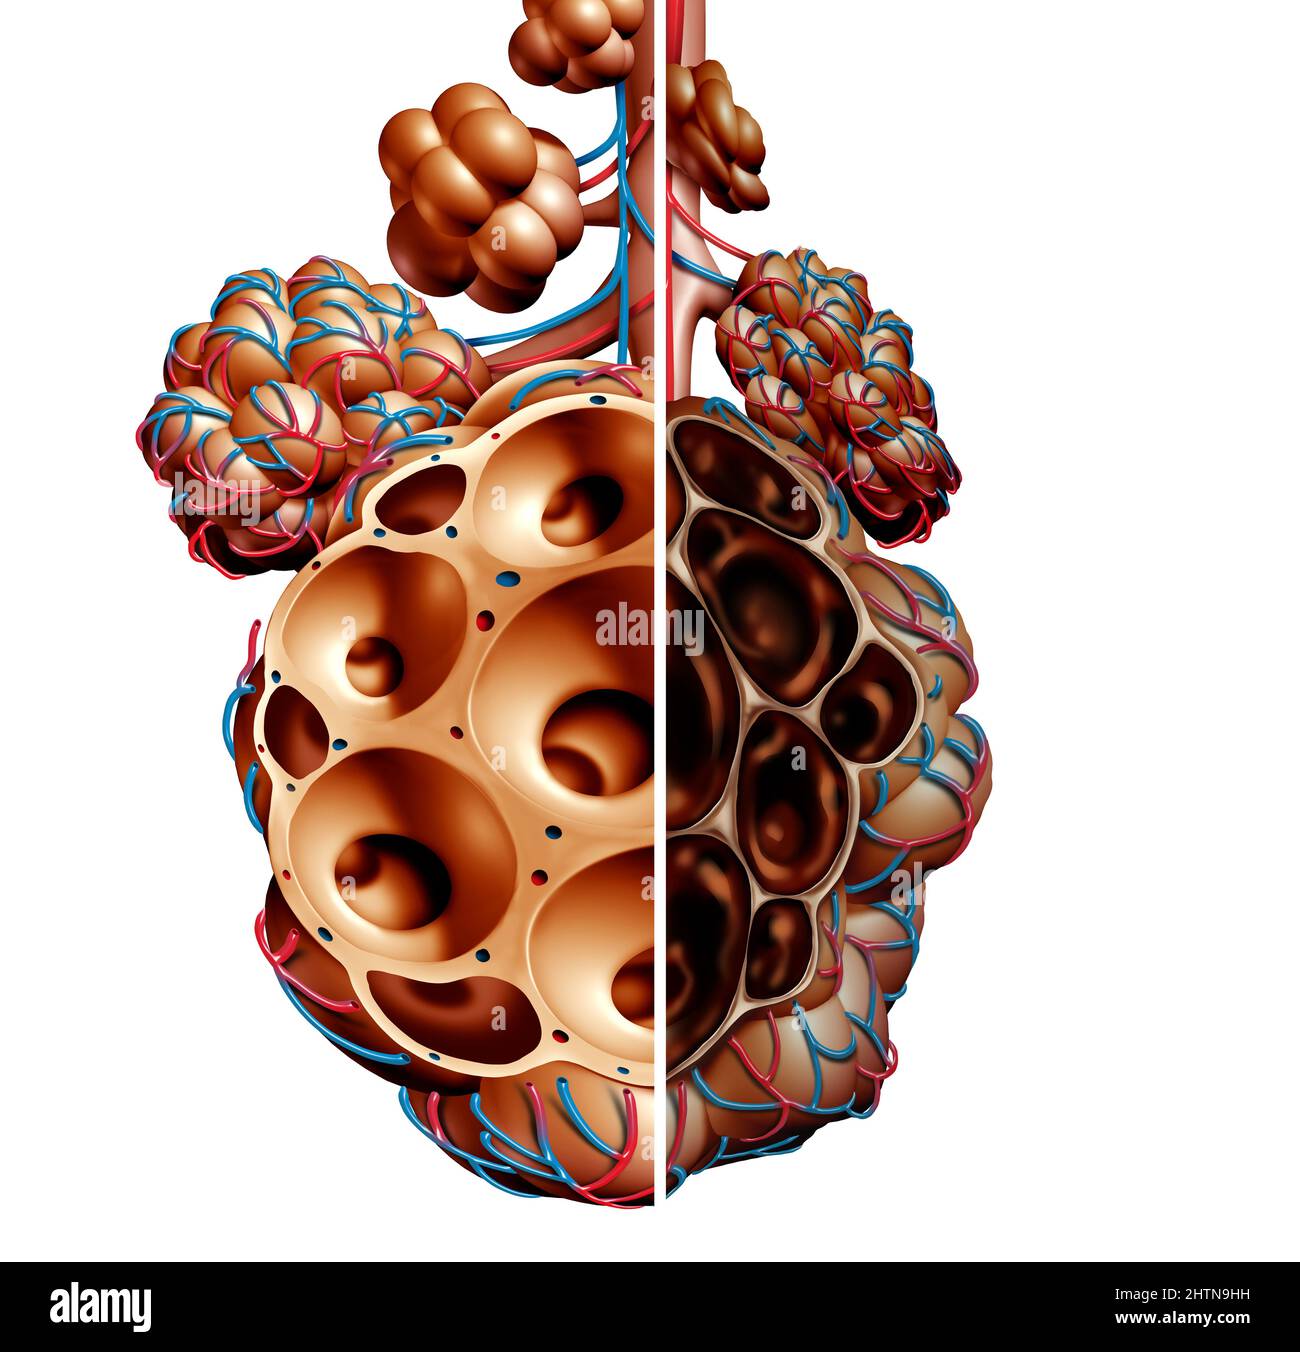

RF2HTN9HH–Emphysème comme essoufflement, trouble pulmonaire comme maladie de MPOC et maladie pulmonaire obstructive chronique concept comme bronchioles et alvéoles